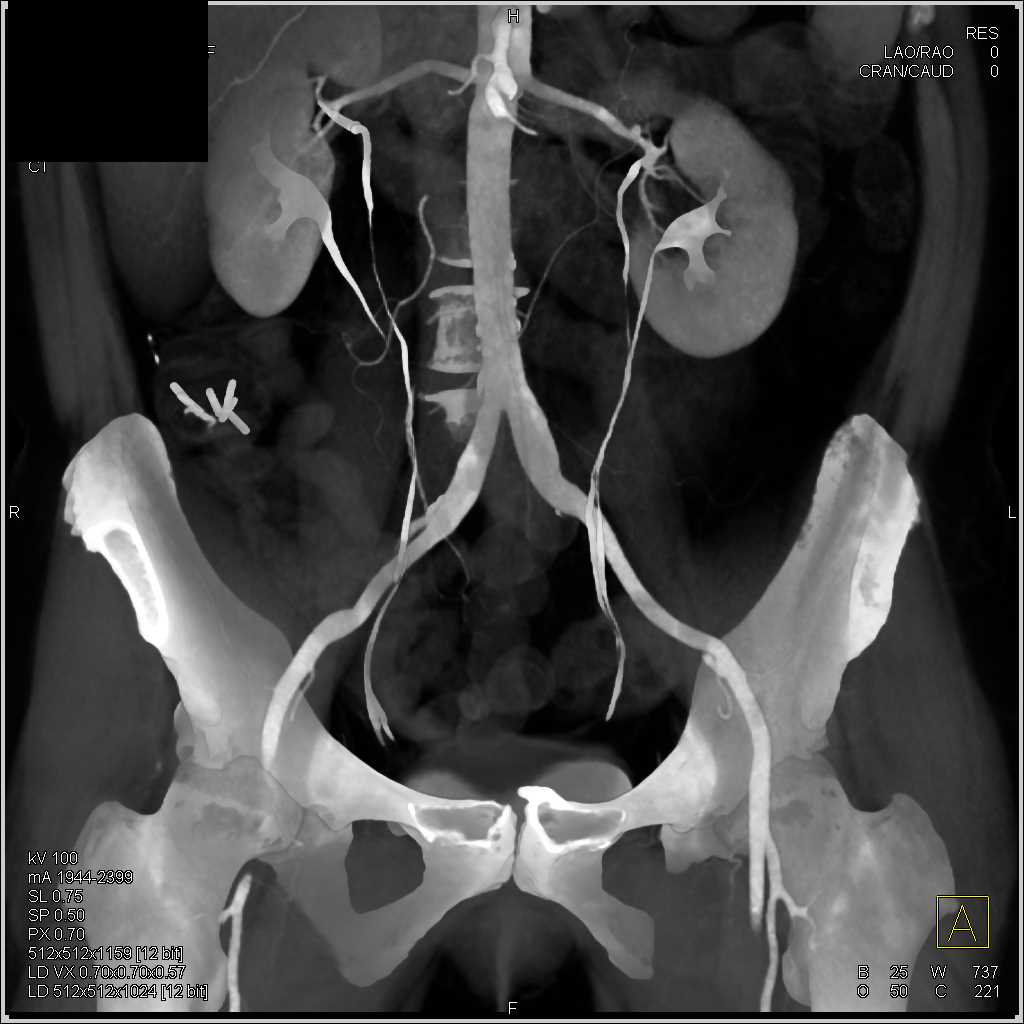

SMA Stenosis